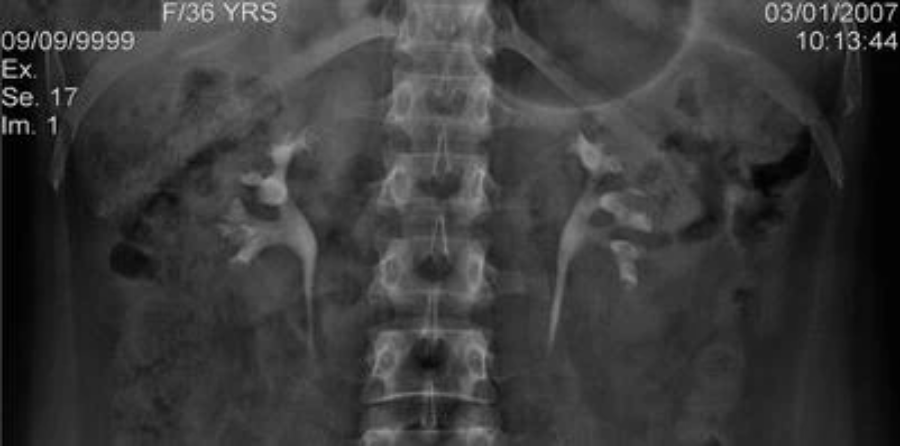

初始进入肾脏的计划和成功执行对 PCNL 的结果至关重要。能够以最少的并发症进入所需的肾盏,需要对肾脏解剖结构和周围结构有透彻的了解。肾脏位于脊柱水平 T12 和 L2/3 之间的腹膜后(图41.1)。右肾通常比左肾低 2-3 厘米。尽管每个肾脏的很大一部分实际上是肋上的,但下极几乎总是在肋下。4各肾斜卧,长轴与腰大肌外侧缘平行,使上极肾盏比下极更靠内侧和靠后。在横向平面中,肾脏向后倾斜 30°。除此之外,每个肾脏随着呼吸向头尾方向移动;这种运动有时非常广泛,在全身麻醉下可能会增加(但也可以控制)。

肾脏解剖:CT 尿路重建图像,显示左侧双工系统的肾脏定位

肾脏解剖:造影后 10 分钟静脉尿路造影,显示中肾盏组双侧引流到下肾盏组